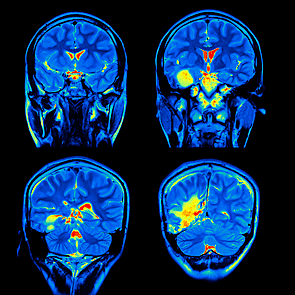

Neuroimagen

Fisiopatología Daño cerebral primario:

Consiste en las lesiones producidas por el propio traumatismo y/o por las fuerzas de aceleración y desaceleración.

Dichas lesiones son escasamente modificables por la intervención terapéutica,siendo la prevención un aspecto fundamental. Las lesiones vendrán determinadas por el lugar del impacto, la dirección de la fuerza, la intensidad y la resistencia tisular • Aceleración lineal laterolateral

Daño cerebral secundario

Consiste en las lesiones producidas

por distintos factores: isquemia (hipotensión, hipoxia, alteración del flujo cerebral…), alteraciones de la función celular (afectación de la permeabilidad de la membrana celular) y alteraciones de las cascadas del metabolismo. Este daño cerebral secundario se desarrolla en las horas siguientes al traumatismo y, a diferencia del daño cerebral primario, puede ser reversible con un buen manejo

terapéutico.